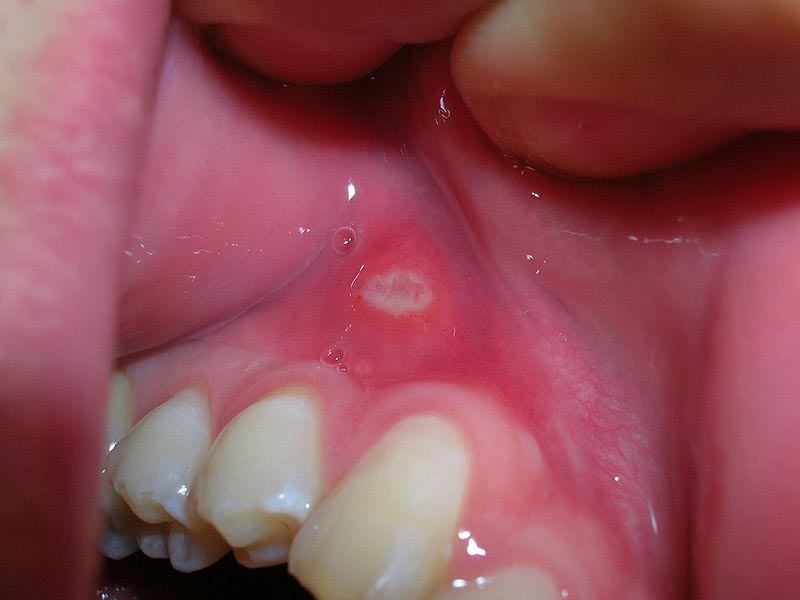

- Afte najčešće započinju kao bijele ili žućkaste ranice s crvenim rubom, a mogu se širiti na veličinu do 2,5 cm u promjeru. Iako su obično male, njihov izgled može biti neugodan, a bol koja ih prati često otežava obavljanje svakodnevnih aktivnosti. Prema informacijama dostupnim na Blicu, afte se obično javljaju na nekoliko ključnih mjesta u usnoj šupljini, uključujući jezike, desni, nepce, unutarnju stranu usana i ispod jezika. U većini slučajeva, afte su jednostavne i nestaju u roku od tjedan dana, međutim, postoji i vrsta afti koja je kompleksnija i može trajati dulje.

Prema informacijama na ordinacija.hr, simptomi afti uključuju pojavu jedne ili više bolnih ranica u usnoj šupljini koje mogu biti bijele, sive ili žute boje, s crvenim rubom. Osim toga, često se javlja osjećaj peckanja ili žarenja na zahvaćenom području. U težim slučajevima, može doći do povišene temperature, iscrpljenosti i otečenih limfnih čvorova. Iako afte prolaze same od sebe, postoje različite opcije za ublažavanje boli i ubrzavanje procesa zacjeljivanja, kao što su lokalni anestetici, ispiranja usta s vodikovim peroksidom ili kortikosteroidne masti.